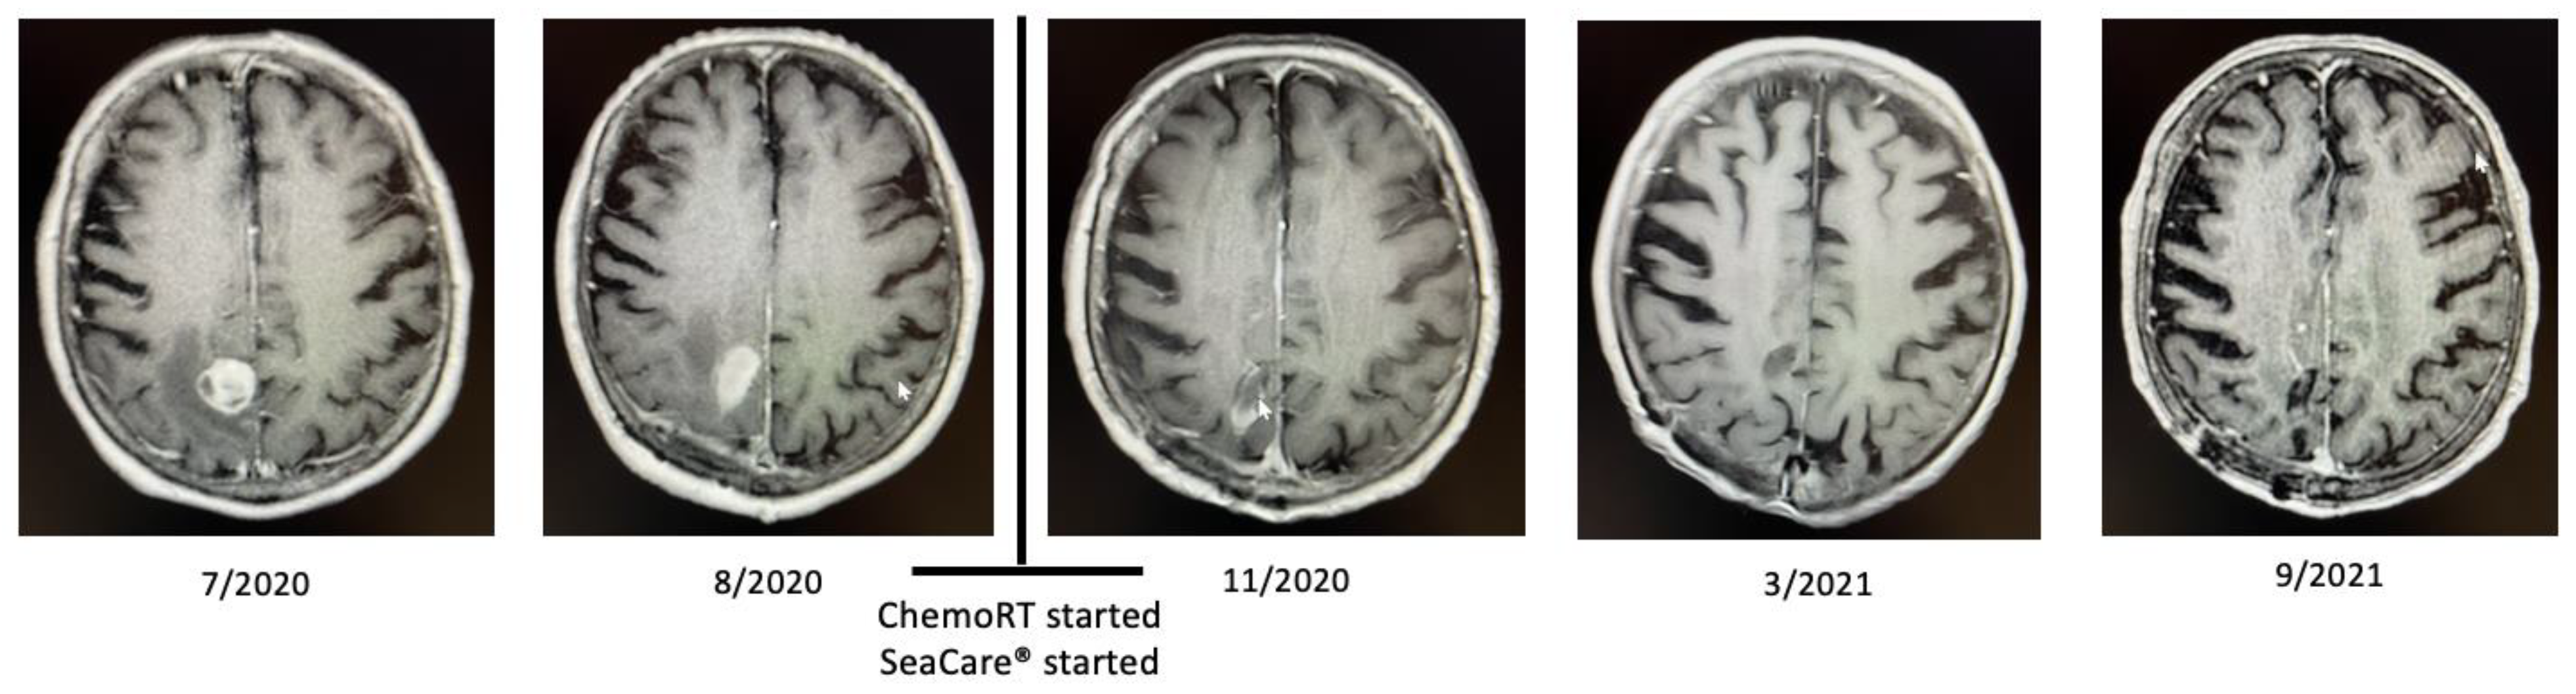

2.1. Patient 1

2.2. Patient 2